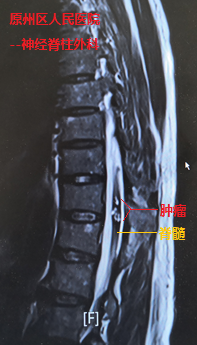

經(jīng)檢查發(fā)現(xiàn),在史伯伯前后徑不到1cm的胸椎脊髓內(nèi),卻有直徑約為1.5cm的腫瘤,并隨著出血膨脹,幾乎占據(jù)了整個(gè)脊髓,導(dǎo)致患者一側(cè)下肢近遠(yuǎn)端肌力完全喪失(0級(jí)),另一側(cè)下肢也僅能勉強(qiáng)移動(dòng)(2-3級(jí))。當(dāng)?shù)?/SPAN>醫(yī)院神經(jīng)脊柱外科主任萬欣龍判斷,史伯伯得的可能是脊髓髓內(nèi)的海綿狀血管瘤,如若不進(jìn)行手術(shù),隨著腫瘤出血后脊髓水腫的加重,患者的病情將進(jìn)一步加重。

我院神經(jīng)外科援寧隊(duì)員鄭小斌在查看患者并詳細(xì)閱片后,與萬欣龍主任交流討論時(shí),考慮到患者管性腫瘤體積大,且生長時(shí)間長達(dá)十余年,導(dǎo)致該腫瘤與脊髓組織的黏連十分嚴(yán)重,最終決定采用顯微鏡下經(jīng)脊髓外側(cè)溝切開脊髓并暴露腫瘤。鄭小斌介紹,術(shù)中對(duì)腫瘤與脊髓邊界的分離是手術(shù)的關(guān)鍵,加上患者病情嚴(yán)重,手術(shù)操作既要精細(xì)輕柔,也需連貫穩(wěn)定。經(jīng)過2個(gè)多小時(shí)手術(shù),萬欣龍與鄭小斌將腫瘤完整地從脊髓內(nèi)切除,完整保留了脊髓的正常結(jié)構(gòu)。鑒于腫瘤體積大,出血后脊髓水腫嚴(yán)重,鄭小斌與萬欣龍還將脊柱椎板切除減壓,并進(jìn)行內(nèi)固定手術(shù)加強(qiáng)脊柱的穩(wěn)定性,手術(shù)順利完成。